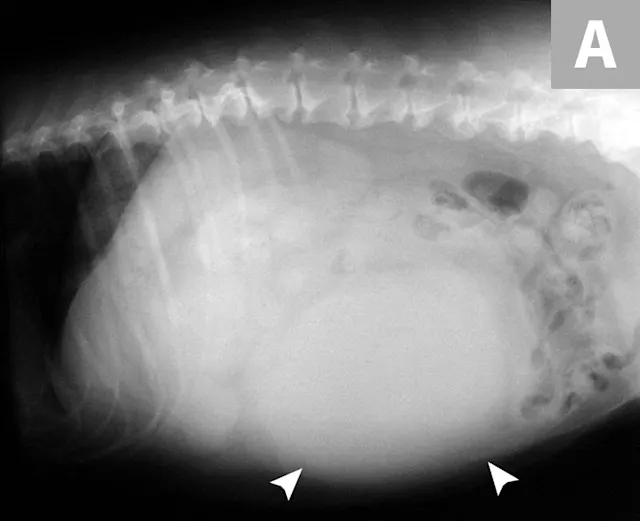

HSA can develop in any vascular organ or tissue but is most commonly found in the spleen (≈50%), right atrium and/or auricle (≈25%), and skin or SC tissue (≈15%; Figure 1).4 Most dogs diagnosed with HSA are geriatric, with a predisposition observed in German shepherd dogs, golden retrievers, and Labrador retrievers.5-7 Splenic HSA is a common splenic malignancy and is accompanied by life-threatening complications (ie, hemoabdomen and distant metastases).8-11 The mode of metastatic spread varies for patients with HSA that involves the abdominal visceral organs (eg, spleen, liver, kidneys). Regional dissemination of disease in the abdominal cavity or retroperitoneal space is enabled by the local deposition of tumor cells following primary tumor rupture, but distant metastasis requires hematogenous circulation, vascular entrapment, and successful colonization of detached tumor cells. Common metastatic sites include the liver, omentum, mesentery, and lungs.7,12 HSA also tends to metastasize to the CNS.13,14

Primary noncutaneous HSA involving the head of the spleen (A) and the right auricle (B, arrowheads). Images courtesy of Laura Garrett, DVM, DACVIM (Oncology), and Louis-Philippe de Lorimier, DVM, DACVIM (Oncology)